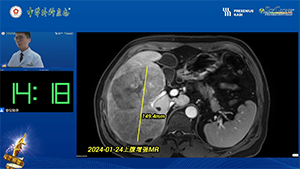

腹腔镜原位解剖性右半肝切除术治疗初始不可切除肝癌

作者:陶海粟 | 作者单位:南方医科大学珠江医院